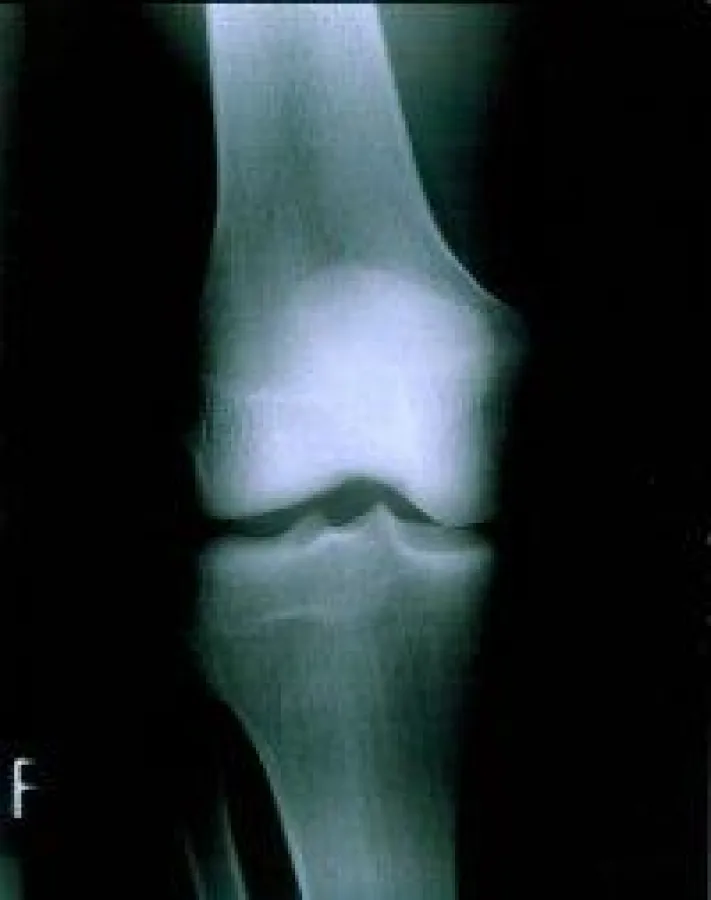

Osteoporose ist charakterisiert durch eine entmineralisierte Knochenmasse, Abnahme des Knochengewebes sowie einer erhöhten Frakturneigung. Frauen ab der Menopause sind von dieser Erkrankung besonders betroffen. Allerdings ist Osteoporose eine Erkrankung, in der die Ernährung eine präventive Bedeutung besitzt.

Der schwedische Arzt Magnus Högström von der Umeå Universität fand einen Zusammenhang zwischen der Kochendichte und der Konzentration von Omega-3-Fettsäuren im Knochen von jungen Männern. In der Studie untersuchte der Wissenschaftler Jungendliche im Alter von durchschnittlich 17 Jahren im Hinblick auf die Knochendichte von Wirbelsäule, Hüfte sowie der Knochendichte des gesamten Körpers. Dabei konnten die Wissenschaftler eine positive Auswirkung zwischen dem Gehalt an Omega-3-Fettsäuren, besonders der Docosahexaensäure, sowie der Knochendichte belegen (1).

Omega-3-Fettsäuren, wie die Eicosapentaensäure sowie Docosahexaensäure, spielen eine wichtige Rolle für die Gesundheit und Vermeidung diverser Erkrankungen. Die Fettsäuren wirken sich positiv auf kardiovaskuläre Erkrankungen, Asthma, Diabetes mellitus Typ 1 sowie multiple Sklerose und rheumatoide Arthritis aus (2). Ferner erhöhen die Fettsäuren die Knochendichte in Jugendlichen und tragen somit wesentlich zur Prävention von Osteoporose im Alter bei. Dieses sind viele Gründe, warum Fisch in einen ausgewogenen Speisplan gehört. 1.715 Zeichen